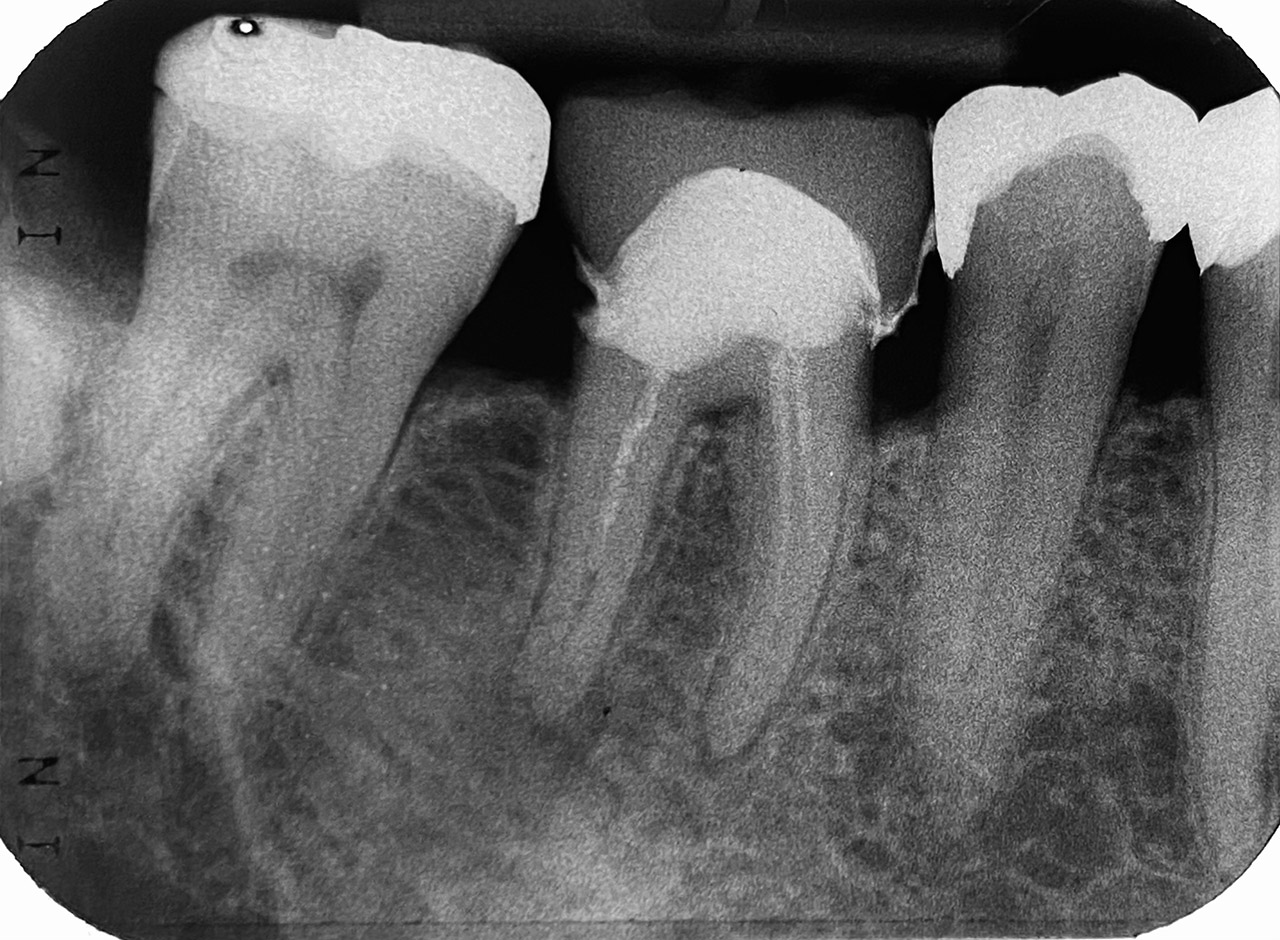

Endodontie/Wurzelbehandlung:

Befund: Aufbißschmerz und Schwellung auf Zahn 46. Frisch zementierte Krone (alio loco).

Therapie: Abnahme der Krone, Entfernung der Zementreste, Revision der insuffizienten Wurzelbehandlung.

Glasfaserstifte und neue Krone, beides adhäsiv zementiert.